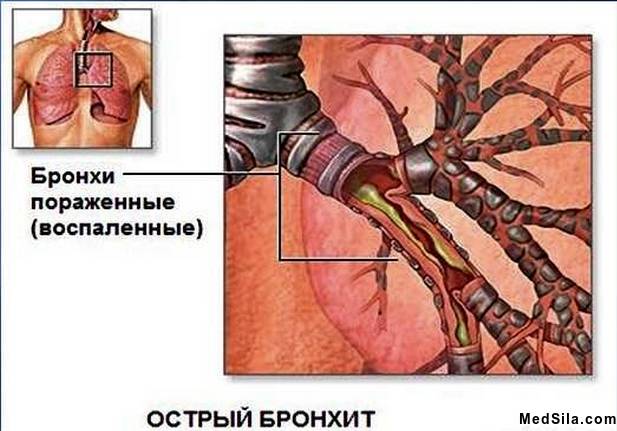

Табачный дым содержит массу ядовитых веществ, которые и оказывают раздражающее действие на слизистую оболочку дыхательных путей, главным образом на трахеи и бронхи. Поэтому в дыхательных путях образуется застойный очаг хронического воспалительного процесса, приводящий к частым простудно-инфекционным заболеваниям, ангинам, бронхитам из-за поражения иммунной системы.

Всем известно выражение «кашель курильщика», ведь действительно , заядлые курильщики мучаются от постоянного сухого кашля, который затем сопровождается отделением большого количества мокроты, и все из-за раздражения слизистой. А длительные нарушения функции слизистой дыхательных путей, приводят к нарушению функции легких и развитию острых (пневмония) и хронических (ХОБЛ, хронический бронхит, бронхиальная астма, эмфизема) заболеваний органов дыхания.